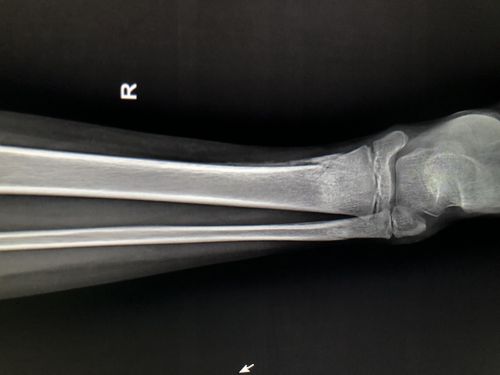

09-2-20治疗后55天.骨痂形成良好,局部无压痛和纵扣痛,去骨牵引.

经过2个月的治疗后复查片可见骨折端对位对线良好,已有骨痂生成.

术后5周骨折处可见骨痂形成

一个月骨痂生长